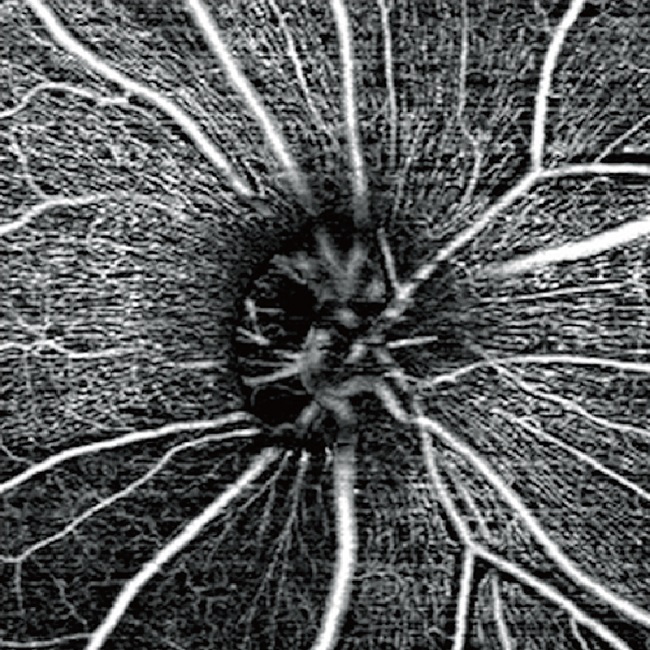

・光干渉断層血管撮影(OCTA)

上述のOCTを用いて、非侵襲的に網膜血管、脈絡膜血管を描出することができます。造影剤を使用しないので、造影剤によるアレルギーや副作用の恐れもなく速やかに検査ができます。主な対象疾患は、加齢黄斑変性、網膜静脈閉塞症、糖尿病網膜症などです。